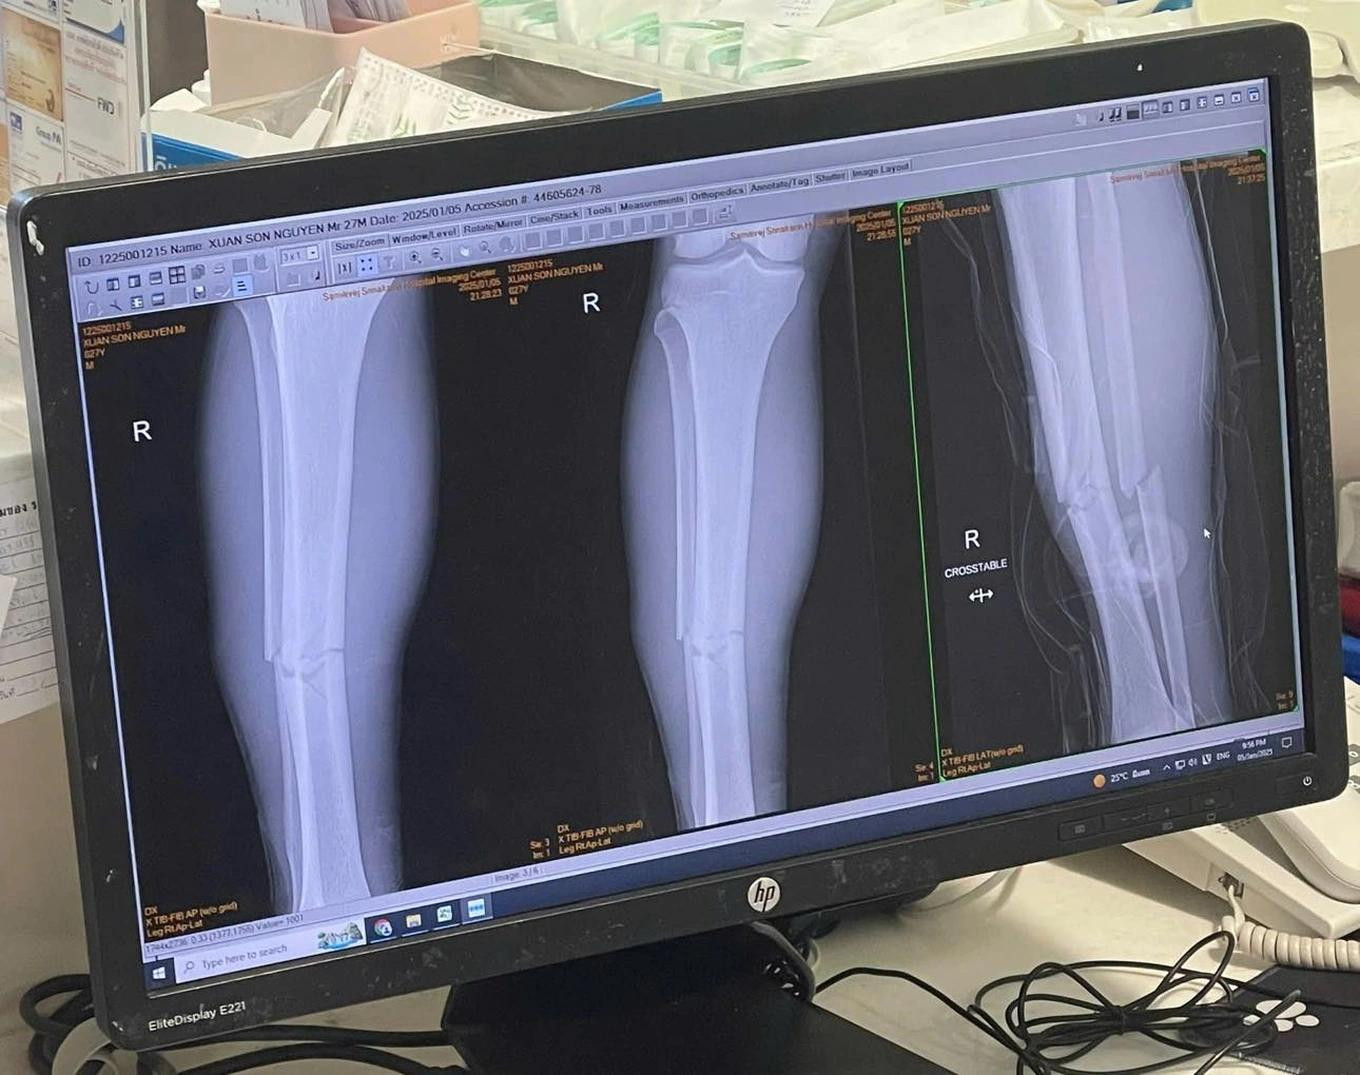

| Hình ảnh chụp phim xương ống đồng bị gãy của Xuân Son. |

Trước đó, Xuân Son đã thi đấu nổi bật và máu lửa trong trận đấu với ĐT Thái Lan nhưng không may bị chấn thương buộc phải rời sân. Tại bệnh viện, các bác sĩ chuẩn đoán cầu thủ này gãy cả 2 xương ở ống chân phải. Vì vậy, cầu thủ sinh năm 1997 sẽ cần có sự điều trị đặc biệt và nhiều thời gian để phục hồi trở lại. Vợ của Xuân Son cũng đã có mặt tại bệnh viện để động viên và chăm sóc cho cầu thủ này.